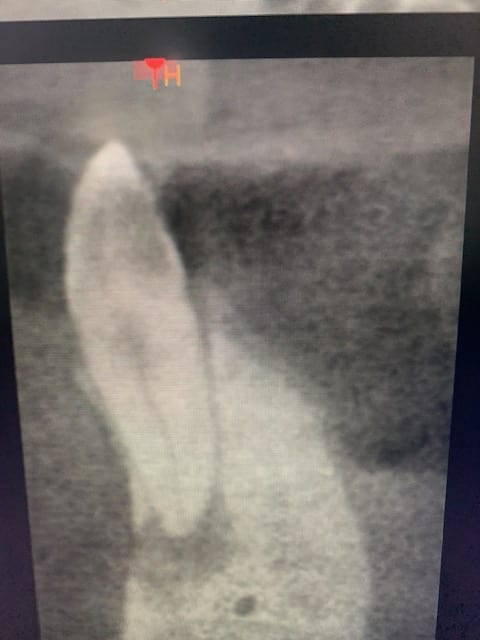

On m’adresse une patiente pour traiter 43 avec image apicale.

43 répond normalement au froid mais a une image apicale radioclaire (attention à bien lire le sujet…).

On me renvoie la patiente pour dépulper 43 vivante ,sans douleur, intacte avec image radioclaire et fenestration de la corticale vestibulaire à l’apex…